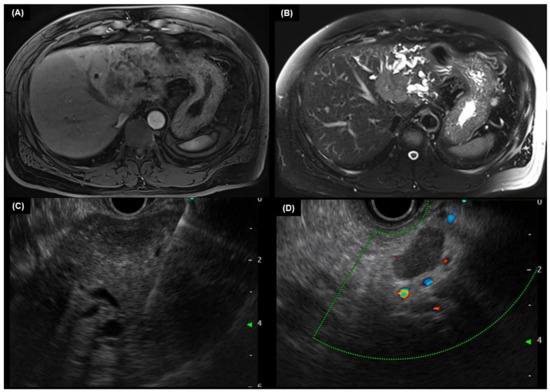

4.3. MRI and MRCP

5.2. Endoscopic Ultrasound

5.3. Intraductal Ultrasound